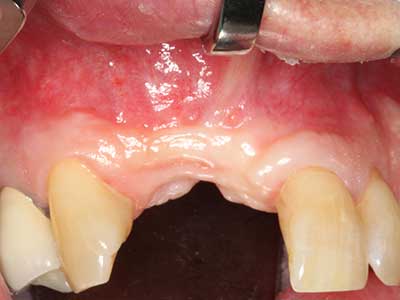

Initial and surgical treatment phases are differentiated in the treatment of marginal periodontitis. In addition to instruction in oral hygiene and motivating patients, both phases should include adequate cleaning of the root surface. In the regenerative setting an open access is generally preferred. The root surface can be cleaned by piezo surgery using special attachments, where instruments with different curvatures are used to reach areas that are difficult to access, such as furcations. The integrated irrigation in the system flushes the detached concrements and bacteria out of the pocket. Specialized systems such as the Piezomed also include application feedback to minimize the ablation of hard dental substance. The greater the pressure on the periodontal attachment the greater the reduction in the amount of ablation.